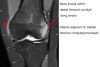

MRI : 슬개골 탈구(Patellar dislocation)

MRI : Acute transient patella dislocation